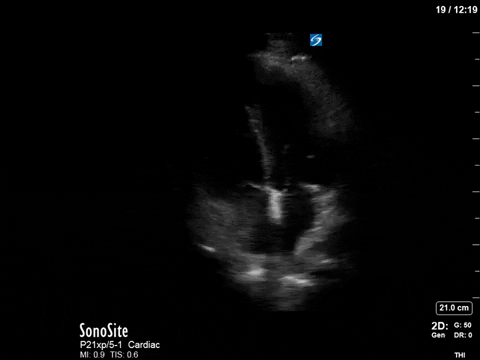

The patient received aggressive volume expansion (with blood products, due to her ongoing bleeding), which immediately substantially reduced her vasopressor requirements (norepinephrine was down to 4; vasopressin was off) and improved her tachycardia (HR now in the 90s). Given this dramatic improvement, the ICU team held off on the addition of beta-blockers. A repeat POCUS scan was done 12 hours later, which revealed the following:

As you can see, there is no longer aliasing in the LVOT PW tracing, and we can now measure cardiac output. In this case, VTI/cardiac output was high, consistent with corrected hypovolemia and and ongoing low-SVR state (cirrhosis). However, we no longer have an elevated pressure gradient.